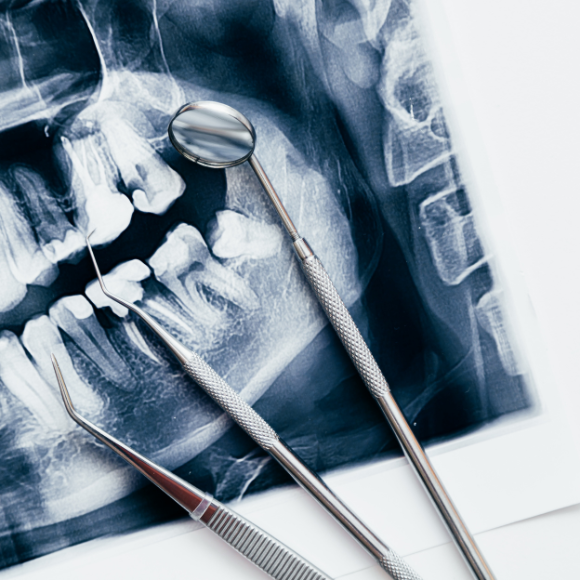

13-10 - O que acontece ao fazer tratamento sem exame?

Diagnóstico Incorreto

Sem um exame adequado, o dentista pode não identificar corretamente a causa do problema, levando a um tratamento ineficaz ou inadequado.

Tratamento Incompleto

Podem ser negligenciados problemas subjacentes, como cáries ocultas, infecções, ou doenças gengivais, que podem piorar com o tempo.

Complicações

Sem uma avaliação completa, há um risco maior de complicações durante ou após o tratamento, como infecções ou reações adversas.

Desperdício de Tempo e Dinheiro

Um tratamento mal direcionado pode resultar em necessidade de tratamentos adicionais, aumentando os custos e prolongando o tempo de recuperação.

Risco à Saúde Geral

Algumas condições bucais podem estar ligadas a problemas de saúde mais amplos. Sem uma avaliação adequada, esses riscos podem passar despercebidos, afetando a saúde geral do paciente.